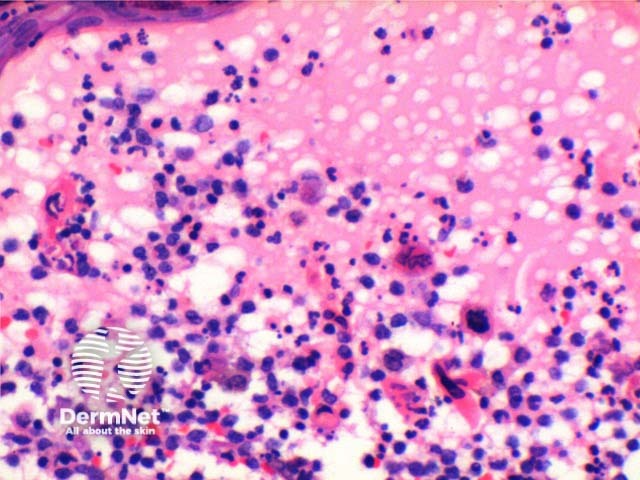

The histology of herpes infections is very distinctive. The low power pattern of a typical lesion is of an intraepidermal blister (Figure 1). The key feature is acantholysis with solitary keratinocytes within the blister cavity (Figures 1,2,3). Keratinocytes will show nuclear changes in viral infection. These included margination of the nuclear chromatin, multinucleation and nuclear inclusions (Figures 3,4,5). The viral inclusions are small pink deposits with a clear halo seen within the nucleus. When present in herpes virus infection and present with the other nuclear changes of this infection they are called Cowdry Type A inclusions. Cowdry Type B inclusions are associated with other infections such as poliovirus and do not have the other nuclear changes of herpes infection.

Early changes of vacuolation in the cytoplasm may be seen along the basal keratinocytes. As the cells swell and separate, the cytoplasm becomes eosinophilic, particularly notable in the multinucleated cells. The inflammatory infiltrate is mixed, predominantly lymphocytes and neutrophils with scattered eosinophils frequently seen (Figure 6).

Figure 3